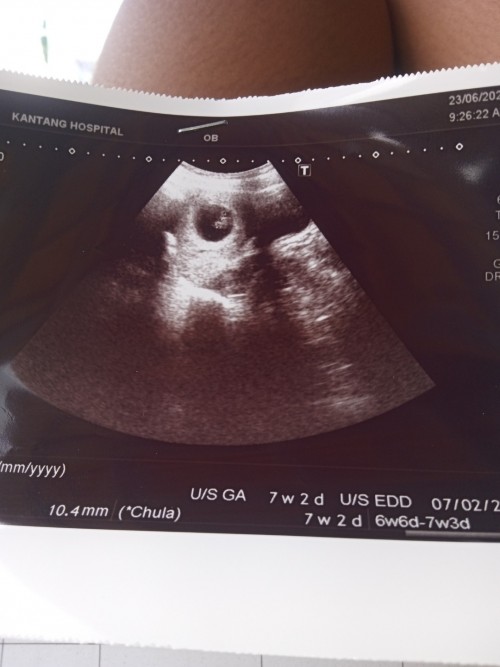

บ้านนี้ไปซาวด์ตอน7สัปดาห์